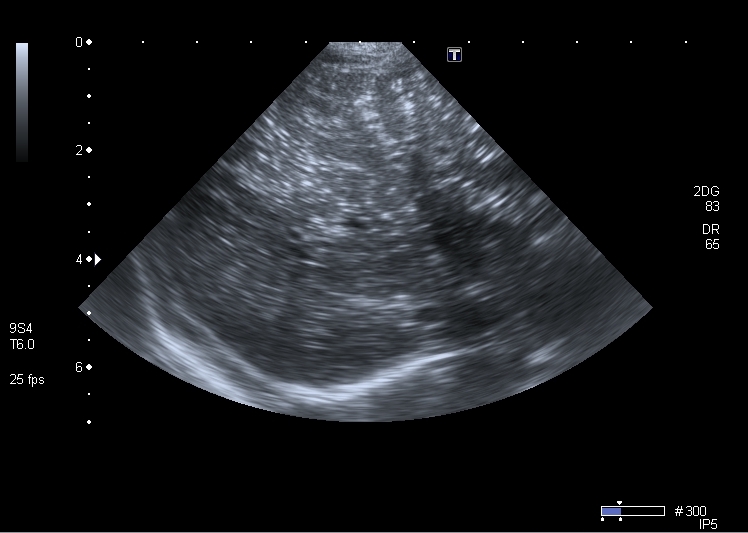

Хочу продолжить дискуссию, повод для этого - сегодняшний пациент 1 года 4 месяцев с клиникой кишечной инфекции и подозрением на инвагинацию. Инвагината не нашёл, но зато при УЗИ выявлены следующие изменения в печени

Кроме того был выражен феномен спонтанного контрастирования кровотока в портальной системе (пузырьки газа?). На рентгенограмме - единичные горизонтальные уровни в тонкой кишке, интерстициального пневматоза стенки газа в проекции портальной системы нет.

На УЗИ - множественные гиперэхогенные включения в печени.

Через 2 дня живот опал, на УЗИ - нормальная печень. Признаков некроза кишечника не было.

Рискну высказать предположение о возможности проникновения газа в портальную систему через неповреждённую, но восппалённую стенку кишки на фоне избыточного давления в её просвете .